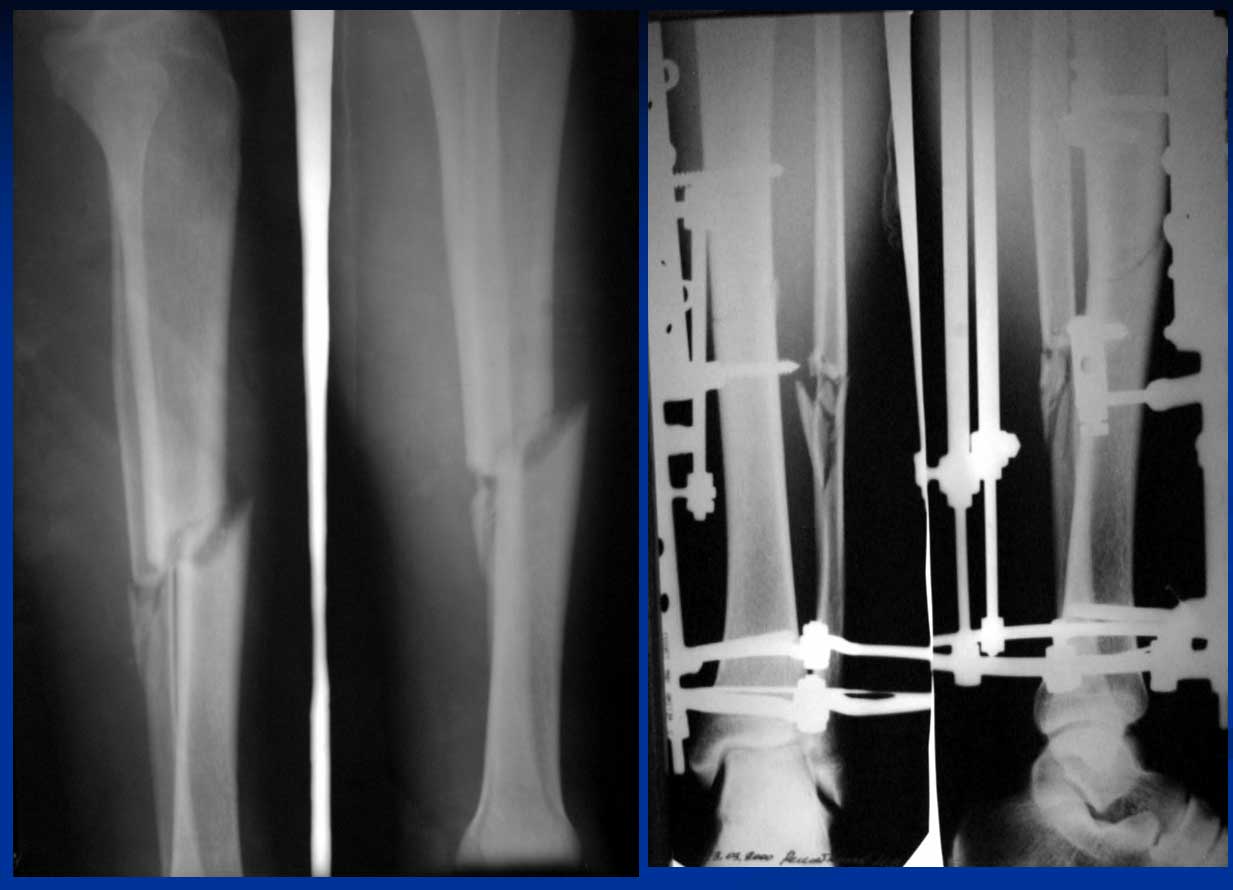

Клинический пример, демонстрирующий описанную технологию, представлен на рентгенограммах (рис. 7). Пациент 30 лет получил поперечный перелом костей голени в средней трети диафиза во время спортивных соревнований в результате удара ногой по голени. При поступлении выполнен остеосинтез спице-стержневым аппаратом. Через 2 месяца демонтирован спицевой модуль, еще через месяц снят монолатеральный аппарат. Общий срок пребывания в аппарате составил 3 месяца.

рис. 7. Рентгенограммы пациента с косопоперечным диафизарным переломом костей голени, которому был выполнен остеосинтез спице-стержневым аппаратом (а - до лечения, б - после остеосинтеза, аппарат включает спицевой модуль, в - перед снятием аппарата в срок три месяца, спицевой модуль демонтирован месяц назад; г - результат в четыре месяца).